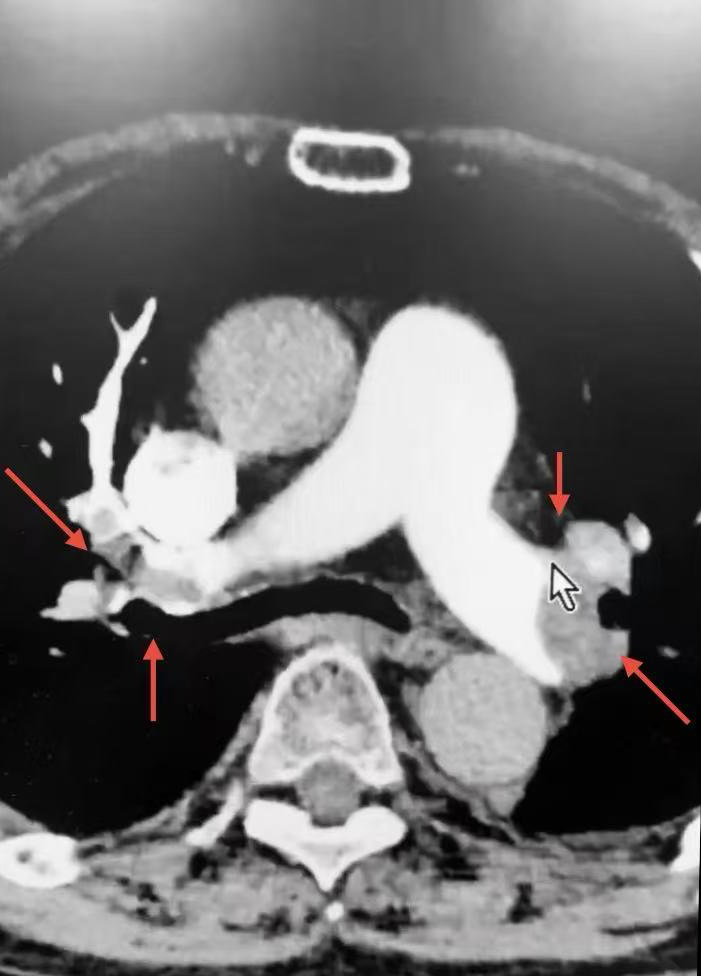

患者CT提示肺动脉主干血栓、双肺动脉主干及一、二级分支多发栓塞